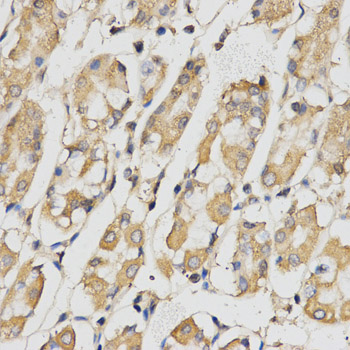

Immunohistochemistry of paraffin-embedded human kidney cancer using RACGAP1 antibody at dilution of 1:200 (x400 lens)